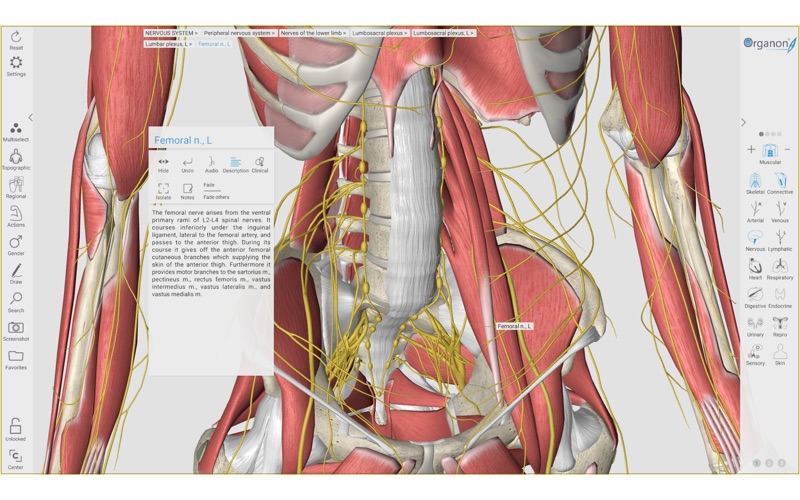

2. 3D Organon Anatomy is an interactive anatomical atlas featuring all 15 human body systems.

5. All anatomical definitions and clinical correlations are written by professors of anatomy and medical professionals.

6. It features all body systems: Skeletal, Connective, Muscular, Arterial, Venous, Nervous, Lymphatic, Heart, Respiratory, Digestive, Endocrine, Urinary, Reproductive, Sensory organs, and Integumentary (skin).

10. 3D Organon unfolds life-like high resolution 3D models covering every aspect of the human body.